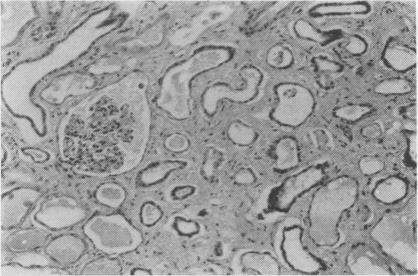

RENAL PAPILLARY NECROSIS AND PHENACETIN: TWO FURTHER CASES.

Postgrad Med J. 1965 Aug;41(478):498-500. doi: 10.1136/pgmj.41.478.498.